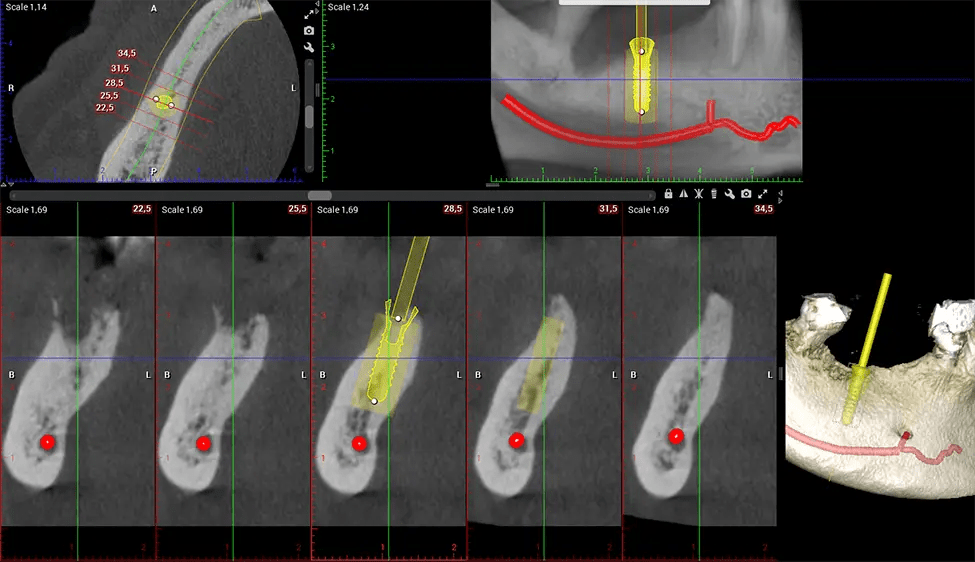

Another significant benefit is that 3D imaging provides more precise images of your bone structure. These images are more detailed, providing you with a more accurate diagnosis. An accurate diagnosis means better treatment for you.

When paired with extractions, dental implant placement, or bone grafting, CBCT technology can provide you with a quicker and much more comfortable experience. This is because the 3D image provides a more detailed picture of your entire oral cavity, allowing your dentist to walk you through each step of the process before it occurs. This often helps patients feel more prepared and comfortable overall, especially if they have had a traumatic experience with past dental treatments.

Oral and Maxillofacial Surgeon Complex oral surgeries, orthognathic (jaw) surgery, and removal of impacted teeth. Offers precise, three-dimensional visualization of the skull, jaw, and craniocervical junction to enhance diagnostic accuracy and minimize surgical risks.

Orthodontist Assessing facial asymmetry, planning orthognathic surgery, and managing cleft lip and palate and sleep apnea. Provides a comprehensive view of the craniofacial complex to better plan treatments and evaluate outcomes.